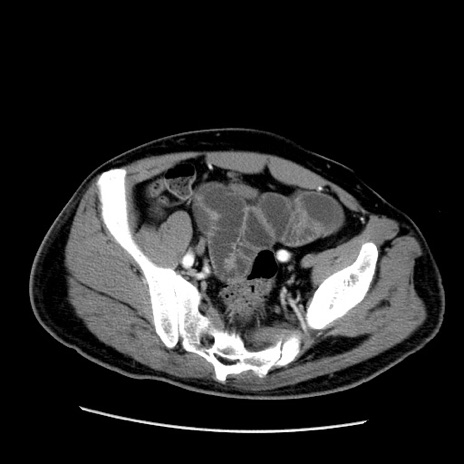

冠状断像

【症例】50歳代男性

【主訴】腹痛

【現病歴】AVMからの被殻出血のため回復期リハ病棟入院中。 本日午後3時頃急に下腹部痛が出現した。

【既往歴】AVM、被殻出血、虫垂炎、高血圧

【身体所見】意識晴明、左半身不全麻痺、会話の理解は良好、36.5°C、腹部:膨隆、全体に板状硬、下腹部正中に圧痛点あり、反跳痛-、筋性防御不明、右下腹部にope scar

【データ】WBC 9400、CRP 0.06